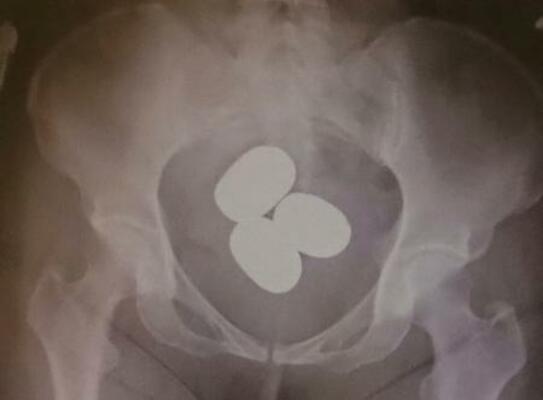

東京税関成田税関支署は24日、粉状の金を避妊具などに入れて体内に隠し、香港から成田空港へ密輸するケースが急増していると明らかにした。今年1~3月に押収しただけで時価総額は約12億円に上る。不安定な国際情勢を背景に金の価格は高騰しており、正規の輸入で納めなければならない消費税を免れ、利ざやを得る目的とみている。

成田税関支署によると、成田空港で粉状の金の摘発は昨年1年間で23件、計約31キロ。今年は3月までに30件、計約45キロで、いずれも香港や中国籍の旅客が、粉状の金を空港到着後などに体内に隠し、持ち込もうとした。中高年の女性が多く、複数の塊に分けて約2・7キロ分を密輸しようとした男性もいたという。